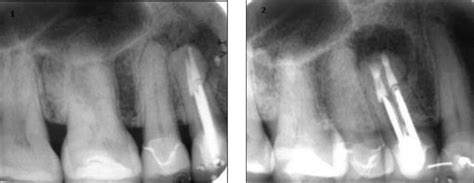

Colocación de microtornillo como anclaje de ortodoncia 2012

Microtornillos en Ortodoncia: Una Herramienta Valiosa

Los microtornillos son un tipo de implante alveolar que proporcionan un método excelente de anclaje. Son un elemento económico, fácil de colocar y retirar. La estabilidad a largo plazo es predecible y fiable y han constituido un impulso para eliminar la cooperación del paciente, además de conseguir resolver problemas relacionados con el control del anclaje dentario.

Entre sus principales indicaciones se encuentran los siguientes movimientos dentarios: intrusión de molares, retrusión de incisivos y de la intrusión de incisivos entre otras. En los últimos años, se han diseñado implantes de dimensiones pequeñas para situarlos en cualquier superficie del proceso alveolar, incluso en áreas interdentales.

Consideraciones al Usar Microtornillos

Como todo elemento que se inserta en la cavidad bucal, es necesario hacer un estudio radiográfico exhaustivo. No debemos olvidar que estos implantes se colocan entre raíces o en zonas próximas de los dientes. Se han reportado numerosos artículos sobre la lesión periodontal y radicular al insertarlos, éste es el motivo por el cual daremos importancia a este aspecto y detallaremos el procedimiento a seguir en la planificación de la técnica y en las complicaciones que pueden surgir si no se lleva a cabo.